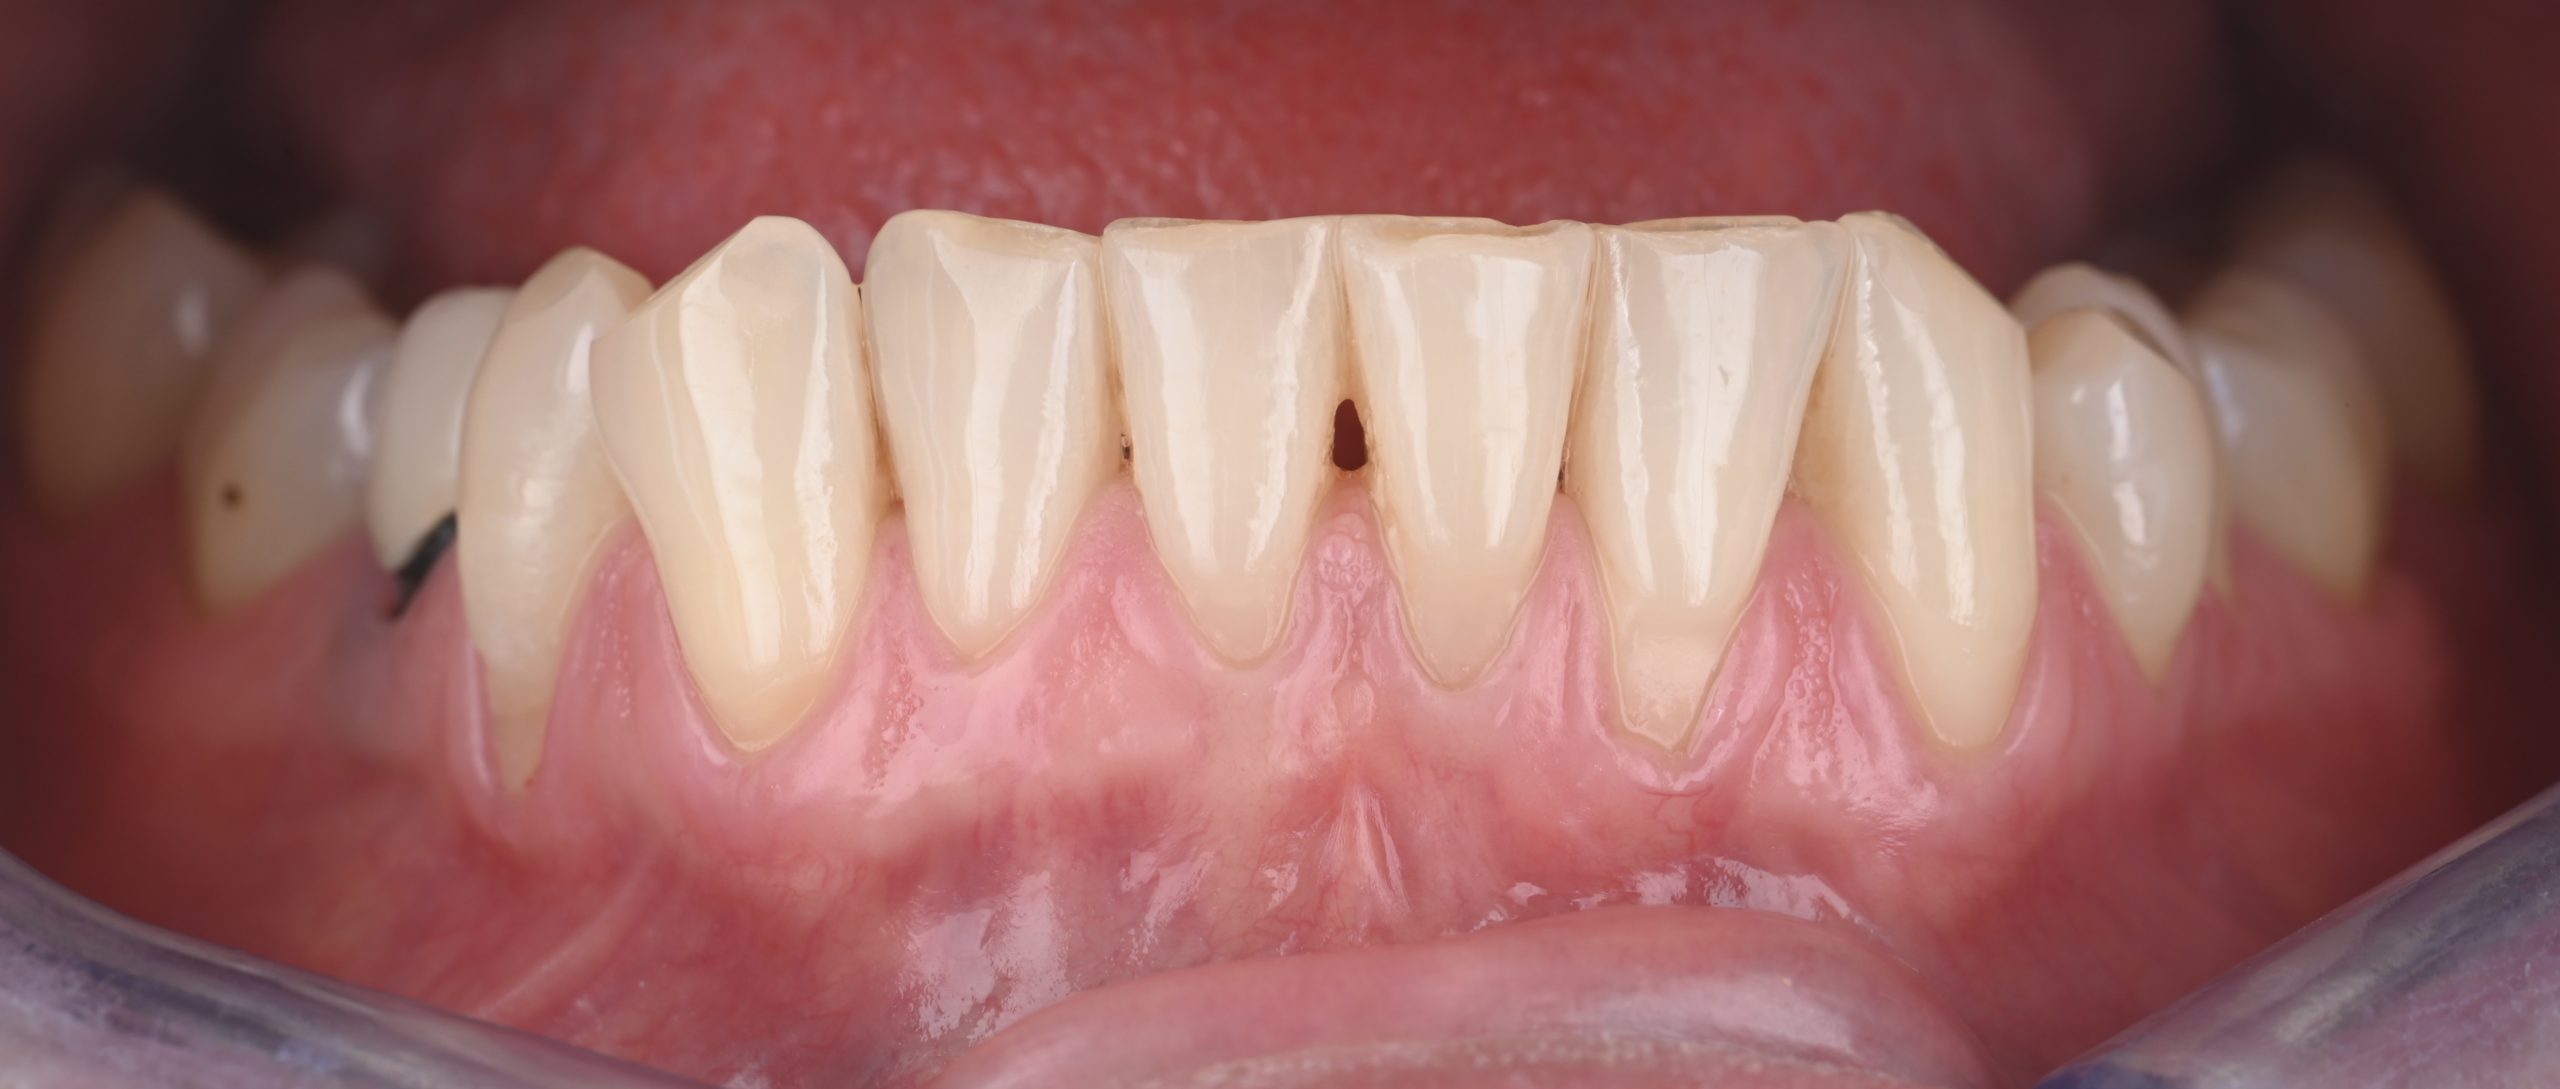

Après

After